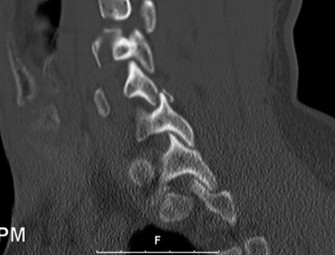

Had the patient been compliant with follow-up during his initial presentation, advanced imaging such as a Single Photon Emission Computed Tomography (SPECT) scan or a Magnetic Resonance Imaging (MRI) scan with Short Tau Inversion Recovery (STIR) sequences would have been indicated. These modalities are highly sensitive for detecting acute stress reactions and marrow edema in the pars interarticularis before a frank fracture line becomes visible on plain radiographs. An MRI at that early stage would have likely shown high signal intensity in the bilateral L5 pars regions on T2-weighted STIR images, confirming an active, metabolically "hot" lesion that possessed a high potential for healing with rigid bracing.

To evaluate the neural elements and the soft tissue structures, a comprehensive MRI of the lumbar spine without contrast was obtained. The T2-weighted sagittal and axial sequences confirmed the Grade 2 anterolisthesis and demonstrated severe bilateral foraminal stenosis at L5-S1. The exiting L5 nerve roots were severely compressed between the hypertrophied, fibrocartilaginous pseudarthrosis tissue of the pars defect dorsally, and the bulging, degenerated L5-S1 disc and superior endplate of S1 ventrally. Furthermore, the MRI revealed Modic Type II changes (fatty replacement of the subchondral bone marrow) in the adjacent vertebral endplates, confirming chronic biomechanical stress and discogenic degeneration. The central canal remained relatively patent, which is characteristic of isthmic spondylolisthesis, as the posterior neural arch is left behind during the anterior translation of the vertebral body.

Clinical & Radiographic Imaging Archive